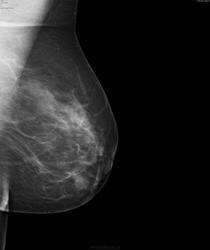

- https://radiomed.ru/sites/default/files/styles/case_slider_image/public/user/17752/bil3.jpg?itok=9Qi9tjtO

Слева опухолью Справа сгрукированые кальцинаты BIRADS 4 с двух сторон

Наш маммограф бы такие микрокальцинаты не нашел)) И как теперь ее будут лечить, интересно? Обе м.ж. прооперируют?

Барышня пока исчезла из поля зрения. Если будет информация обязательно напишу.